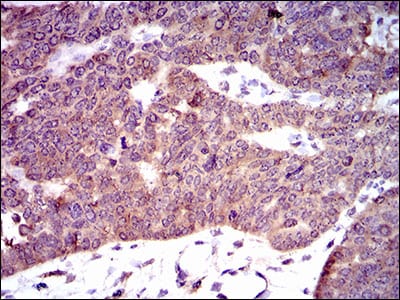

分类: 科研抗体货号: 30464A别名: PDE1B1; PDES1B应用: IHC,FCM反应种属: Human